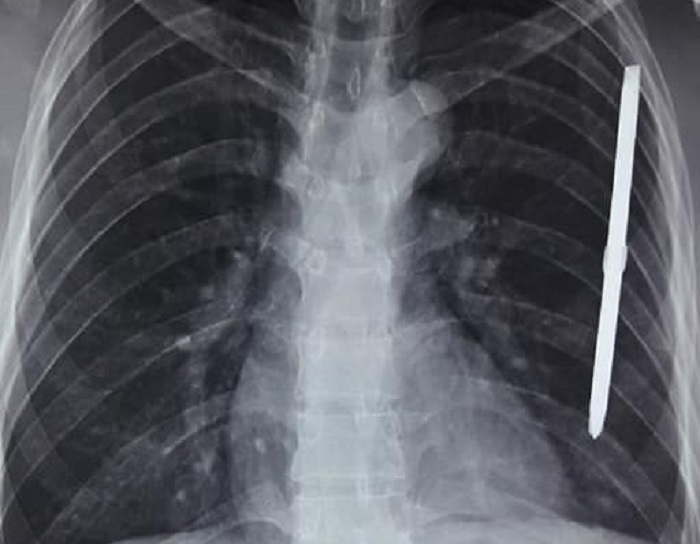

Hình ảnh chụp XQ cho thấy dị vật cắm sâu ở ngực trái của bệnh nhân.

Kết quả chụp X-quang cho thấy có dị vật trong lồng ngực. Bệnh nhân nhanh chóng được chuyển lên Khoa Ngoại tổng hợp để mổ cấp cứu, dẫn lưu màng phổi, lấy dị vật ra khỏi cơ thể.